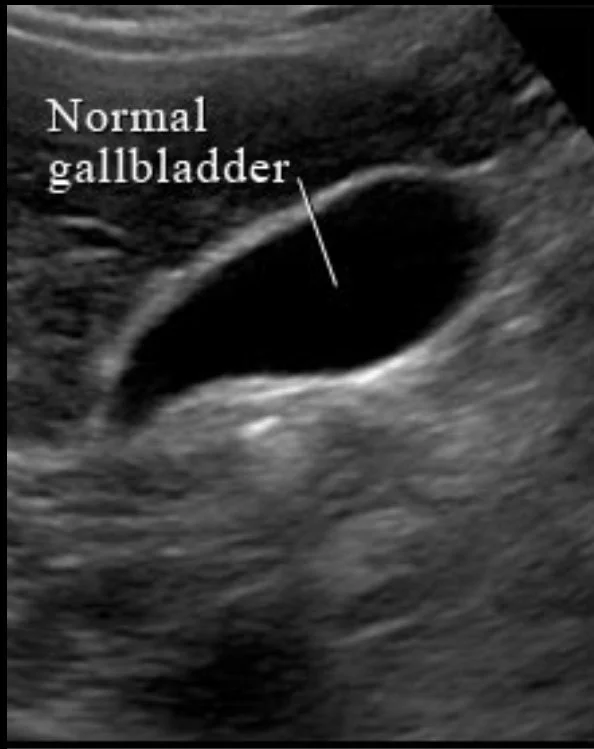

Gallstones are one of the most frequent findings we see in patients attending our private abdominal ultrasound service in Portsmouth and Warsash in Hampshire. Ultrasound is the best test for gallstones and gallbladder-related problems, particularly in people with right upper abdominal pain, bloating, or symptoms linked to eating.

Ultrasound is also extremely useful for assessing the liver, especially when blood tests show abnormal liver function. Fatty liver disease, liver enlargement, and cysts are commonly identified. The kidneys can be assessed for stones, cysts, or obstruction, and the spleen can be checked for enlargement or focal abnormalities.